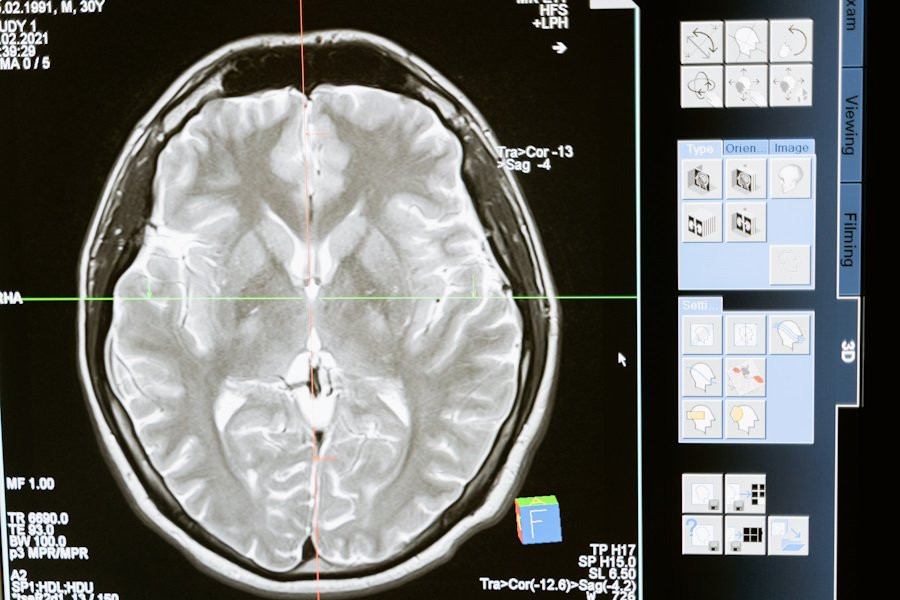

Группа ученых в ходе исследования выявила важную причинно-следственную связь между полимеризацией актина, структурными изменениями в дендритных шипиках и процессами памяти у мышей. Это открытие предлагает новый взгляд на механизмы, лежащие в основе формирования и сохранения памяти в мозге.

Согласно публикации на Science Advances, синаптическая пластичность, способность мозга изменять свою структуру в ответ на опыт и обучение, считается ключевым фактором формирования памяти. Однако, до недавнего времени не было четкого понимания о том, каким образом полимеризация актина, ответственная за стабильность дендритных шипиков - важных структурных элементов нейронов, связанных с образованием синапсов, влияет на кодирование памяти.

Исследователи использовали специально созданную форму протеинкиназы LIMK1, которая направленно воздействует на ADF/кофилин, ключевой модификатор актина. После активации этой формы LIMK1 в организме мышей, было отмечено долговременное увеличение дендритных шипиков и усиление синаптической передачи в гиппокампе, области мозга, играющей важную роль в формировании памяти.